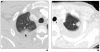

Results: The most common chest CT findings in this case series were pleural effusions and internal mammary and cardiophrenic lymphadenopathy. Pulmonary parenchymal findings included peripheral lung nodules of 1-3.5 cm in size with surrounding ground-glass opacity; many nodules had a linear track to the pleural surface that may correspond to the worm's burrow tunnel. Pericardial involvement (5/8 patients) and omental inflammation (5/7 patients), which are uncommon in Asian paragonimiasis, were common in this series.

Conclusion: Pleural and pulmonary features of North American paragonimiasis are generally similar to those reported from Asia. The presence of a track between a pulmonary nodule and the pleura may help distinguish paragonimiasis from mimickers, including chronic eosinophilic pneumonia, tuberculosis, fungal infection, or malignancy. Pericarditis, lymphadenopathy, and omental inflammation were more common in our series than in reports on paragonimiasis from other regions. These differences may be related to the infecting parasite species or to the fact that radiologic examinations in the present series were performed relatively early in the course of infection.